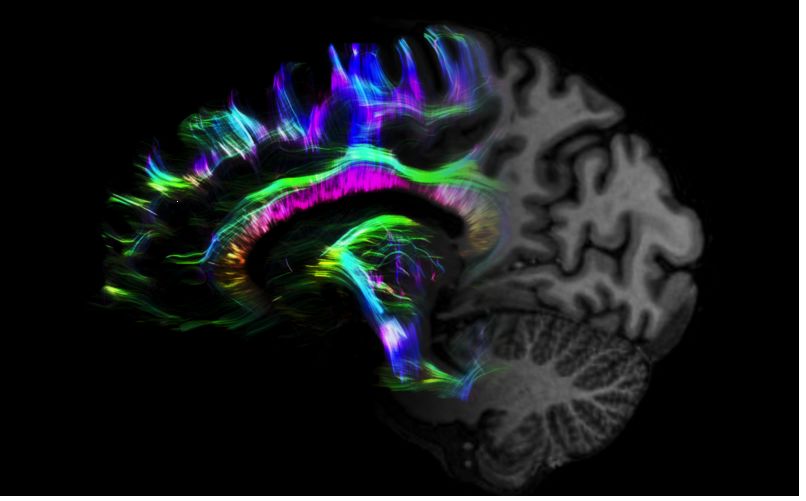

MAGNETOM Terra在業(yè)界首次實(shí)現了兩倍于傳統7T的超強梯度性能,實(shí)現超快速、超高效、超高分辨功能磁共振成像。如此高性能的梯度系統無(wú)論對于科研還是臨床都帶來(lái)了更多可能。

1毫米的各向同性分辨率DTI:神經(jīng)纖維束的交叉細節顯示

但近年來(lái),西門(mén)子與科研機構共同研究發(fā)現,7T提供了數倍于傳統3T磁共振的信噪比和空間分辨率,在神經(jīng)、血管、腫瘤、骨關(guān)節等多個(gè)方面都會(huì )帶來(lái)全新的突破性進(jìn)展。尤其是在目前常規影像設備難以診斷的神經(jīng)退行性疾病如阿茲海默氏病、帕金森病等疾病的發(fā)病機理、早期診斷、治療方案確定以及治療效果評估上,有著(zhù)極大的潛力。